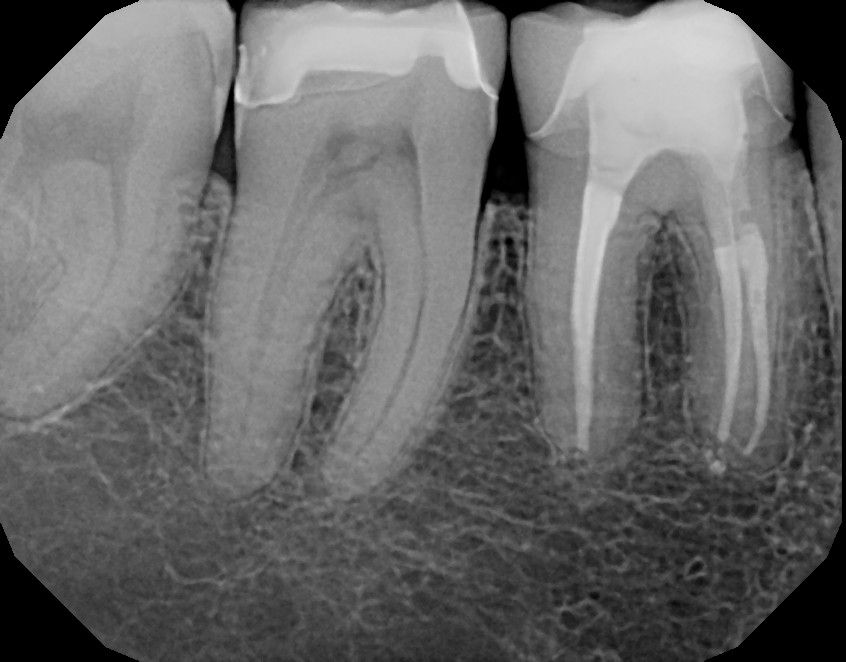

Wenn eine Wurzelbehandlung nicht alle infizierten Bereiche der Wurzelkanäle erfasst hatte, die Wurzelfüllung nicht ausreichend lang und dicht ausgeführt wurde oder der Zahn sich aufgrund einer weiterhin undichten Füllung wieder infizieren konnte, kann es sein, dass die Entzündung im und um den Zahn nicht ausheilt. Man kann dann versuchen, durch eine Wiederholungsbehandlung (Revision) den Zahn zu erhalten. Dazu muss das gesamte alte Wurzelfüllmaterial entfernt werden. Dann wird versucht, die bisher unvollständig aufbereiteten Kanalanteile zu säubern, zu desinfizieren und zu versiegeln. Dank des OP-Mikroskops finden wir auch Wurzelkanäle, die bisher übersehen wurden, und können sie erfolgreich aufbereiten. Trotzdem hat eine Revisionsbehandlung eine deutlich schlechtere Prognose als die Erstbehandlung. Nur wenn wir erwarten, dass wir mit unserer Behandlung Erfolg haben, werden wir Ihnen zu diesem Schritt raten.

Häufig kommen Patienten zu uns, bei denen eine frühere Wurzelkanalbehandlung nicht zum Erfolg geführt hat, d.h. die Entzündung ist nicht ausgeheilt. Wir sehen dann, dass die Wurzelkanalbehandlung nicht vollständig durchgeführt wurde und man davon ausgehen muss, dass noch infiziertes Gewebe in den Wurzeln belassen wurde. Manchmal finden wir auch ein abgebrochenes Instrument in einem Kanal. Auch ein solcher Zahn kann mit entsprechendem Aufwand häufig gerettet werden. Man spricht hier von einer Revisionsbehandlung. Zunächst muss die unvollständige Wurzelfüllung und ggf. auch das Instrumentenfragment entfernt werden. Anschließend werden die Kanäle vollständig aufbereitet und desinfiziert werden, bevor sie dann versiegelt werden können. Die Erfolgsaussichten bei einer Revisionsbehandlung sind schlechter als bei der ersten Wurzelkanalbehandlung, trotzdem lohnt sich die Mühe aber in sehr vielen Fällen.

Kann man eine Wurzelfüllung nicht mehr revidieren oder hat sich durch die Entzündung im Knochen bereits eine Zyste gebildet, bleibt noch die chirurgische Wurzelspitzenresektion. Hierbei wird die entzündete Wurzelspitze unter örtlicher Betäubung abgetrennt, das entzündete Gewebe im Knochen wird entfernt und der Wurzelkanal wird rückwärtig versiegelt. Auch hier ist das Mikroskop ein unersetzliches Hilfsmittel, weil man so den Zugang zur Wurzelspitze klein halten kann und besser beurteilen kann, ob die Wurzel vielleicht gerissen ist.